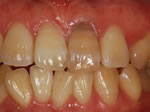

~術前~

オールセラミック修復

~術後~